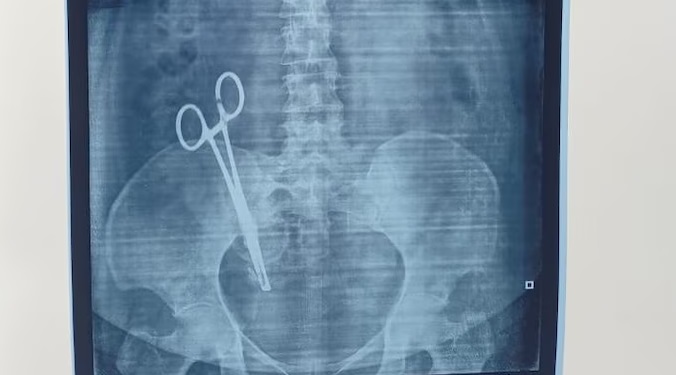

Medical Negligence Kerala : केरल के अलाप्पुझा जिले से चिकित्सा लापरवाही का एक ऐसा मामला सामने आया है जिसे सुनकर कोई भी दंग रह जाए। यहां एक महिला के पेट में डॉक्टर सर्जरी के दौरान आर्टरी फोरसेप्स (एक प्रकार की सर्जिकल कैंची) भूल गए। हैरानी की बात यह है कि यह कैंची महिला के शरीर के अंदर पिछले 5 वर्षों से पड़ी हुई थी।

हाल ही में जब दर्द बर्दाश्त से बाहर हो गया तो उषा ने एक डॉक्टर की सलाह पर गुर्दे की पथरी (Kidney Stone) की जांच के लिए एक्स-रे करवाया। जब एक्स-रे की रिपोर्ट सामने आई तो डॉक्टर और परिजन सन्न रह गए। रिपोर्ट में उषा के पेट के अंदर एक आर्टरी फोरसेप्स (सर्जिकल कैंची) साफ दिखाई दे रही थी।